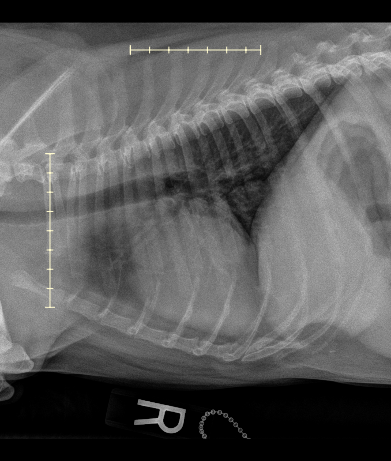

After checking in Gavin and I took a stroll outside, and were called in a few moments later. He and I were taken to a nearby exam room by a technician, and greeted by an oncology team member. After an initial intake and questionnaire, their team took Gavin in the back for a quick check of his mouth, leaving me and my thoughts alone in the room… After ten minutes, their team comes back noting that they’re 99% positive the growth is cancer, possibly melanoma, and that such may have already spread from his mouth to orbital bone / eye socket, and that it may be present in his lungs. At this point my only goal is to obtain information; happy to pay whatever cost for the sedation, needle biopsy, and radiology recommendations.

I leave Gavin in their carefully trained hands. Two hours later I receive a call from their reception team gleefully saying Gavin is awake, and that I may come back to pick him up and chat with the team to discuss their findings. Long story short - cancer is a fibrosarcoma, lungs are clear, and that they expect Gavin to live another three to six months depending on how the tumor continues to grow.